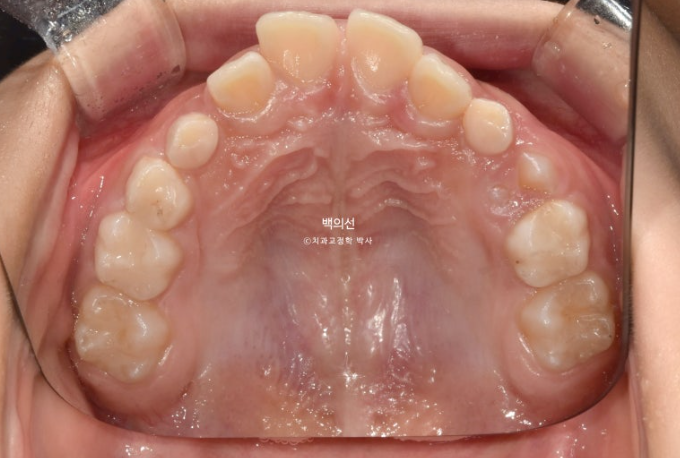

교정치료를 위해 온 만 9세 어린이입니다.

악궁전반부가 좁습니다.

아래도 마찬가지로 악궁확장이 필요합니다.

이 날 공간이 부족하여 앞니가 삐뚤게 나왔고 곧 나올 송곳니는 공간이 부족하여 덧니로 나올 상황입니다.

좁았던 악궁이 넓어지면서 모양이 잡혔고

9개월 후 모습을 보면 송곳니와 작은어금니들이 많이 올라온 게 보입니다.